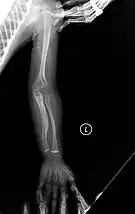

The main symptom of osteogenesis imperfecta is fragile, low mineral density bones; all types of OI have some bone involvement.[5] In moderate and especially severe OI, the long bones may be bowed, sometimes extremely so.[28] The weakness of the bones causes them to fracture easily; a study in Pakistan found an average of 5.8 fractures per year in untreated children.[29] Fractures typically occur much less after puberty, but begin to increase again in women after menopause and in men between the ages of 60 and 80.[1]: 486

- Type V – Having the same clinical features as type IV, it can be clinically distinguished by observing a "mesh-like" appearance to a bone biopsy under a microscope. Type V can be further distinguished from other types of OI by the "V triad": an opaque band (visible on X-ray) adjacent to the growth plates; hypertrophic calluses (abnormally large masses of bony repair tissue) which form at fracture sites during the healing process; and calcification of the interosseous membrane of the forearm,[50] which may make it difficult to turn the wrist.[1]: 429 Other features of this condition may include pulled elbow, and, as in other types of OI, long bone bowing and hearing loss.[64] Cases of this type are caused by mutations in the IFITM5 gene on chromosome 11p15.5.[64][49] The separation of type V from type IV OI, its clinical type, was initially suggested even before its genetic cause was known, by Glorieux et al. in 2000.[50][65] Type V is relatively common compared to other genetically defined types of OI—4% of OI patients at the genetics department of the Brazilian Hospital de Clínicas de Porto Alegre were found to have it.[66]

Diagnosis is typically based on medical imaging, including plain X-rays, and symptoms. In severe OI, signs on medical imaging include abnormalities in all extremities and in the spine.[97] As X-rays are often insensitive to the comparatively smaller bone density loss associated with type I OI, DEXA scans may be needed.[5]: 1514